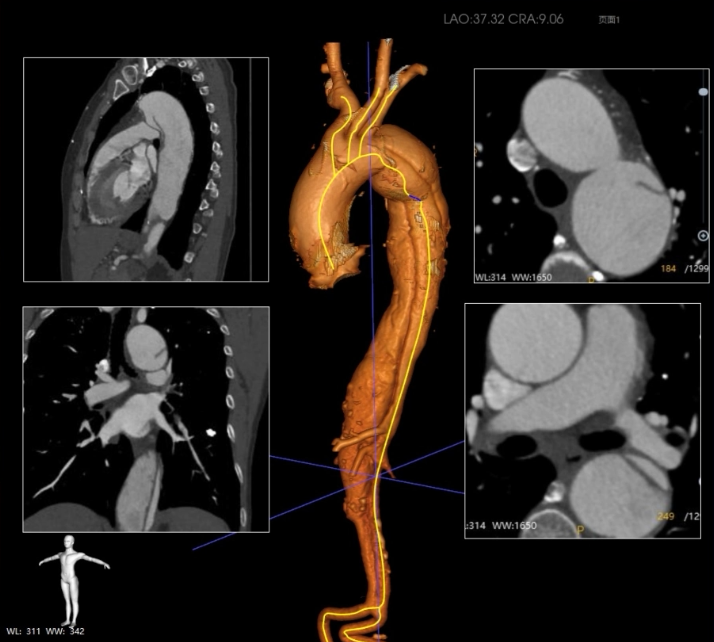

患者为 72 岁女性,因 “发作胸痛三天” 急诊入院。CTA检查结果显示为陈旧性主动脉夹层。夹层向前逆撕累及弓部,范围从左侧锁骨下动脉开口后缘远端延伸至腹主动脉分叉上方。分支血管受累:腹腔干、肠系膜上动脉及左肾动脉由真腔供血,右侧肾动脉由假腔供血。

双侧入路扭曲纤细,最细处右侧髂外直径6.5mm,左侧6mm;降主及腹主真腔严重受压,管腔狭窄。

鉴于患者主动脉弓弓上三分支起始部距离较近,传统单分支主动脉支架置入治疗方案并不适用。

Ⅰ型主动脉弓

弓上三分支起始部距离近

从右侧股动脉入路,使用超滑导丝进入真腔,置入金标猪尾导管造影,再次造影明确夹层真腔位置、形态,可见腹主动脉及降主动脉真腔处多处严重狭窄受压,假腔呈瘤样扩张并累及左侧锁骨下动脉。

根据详细测量数据,选用型号为 F46-40-45-191-16-14-14 FixTa一体化三分支主动脉覆膜支架支架系统。